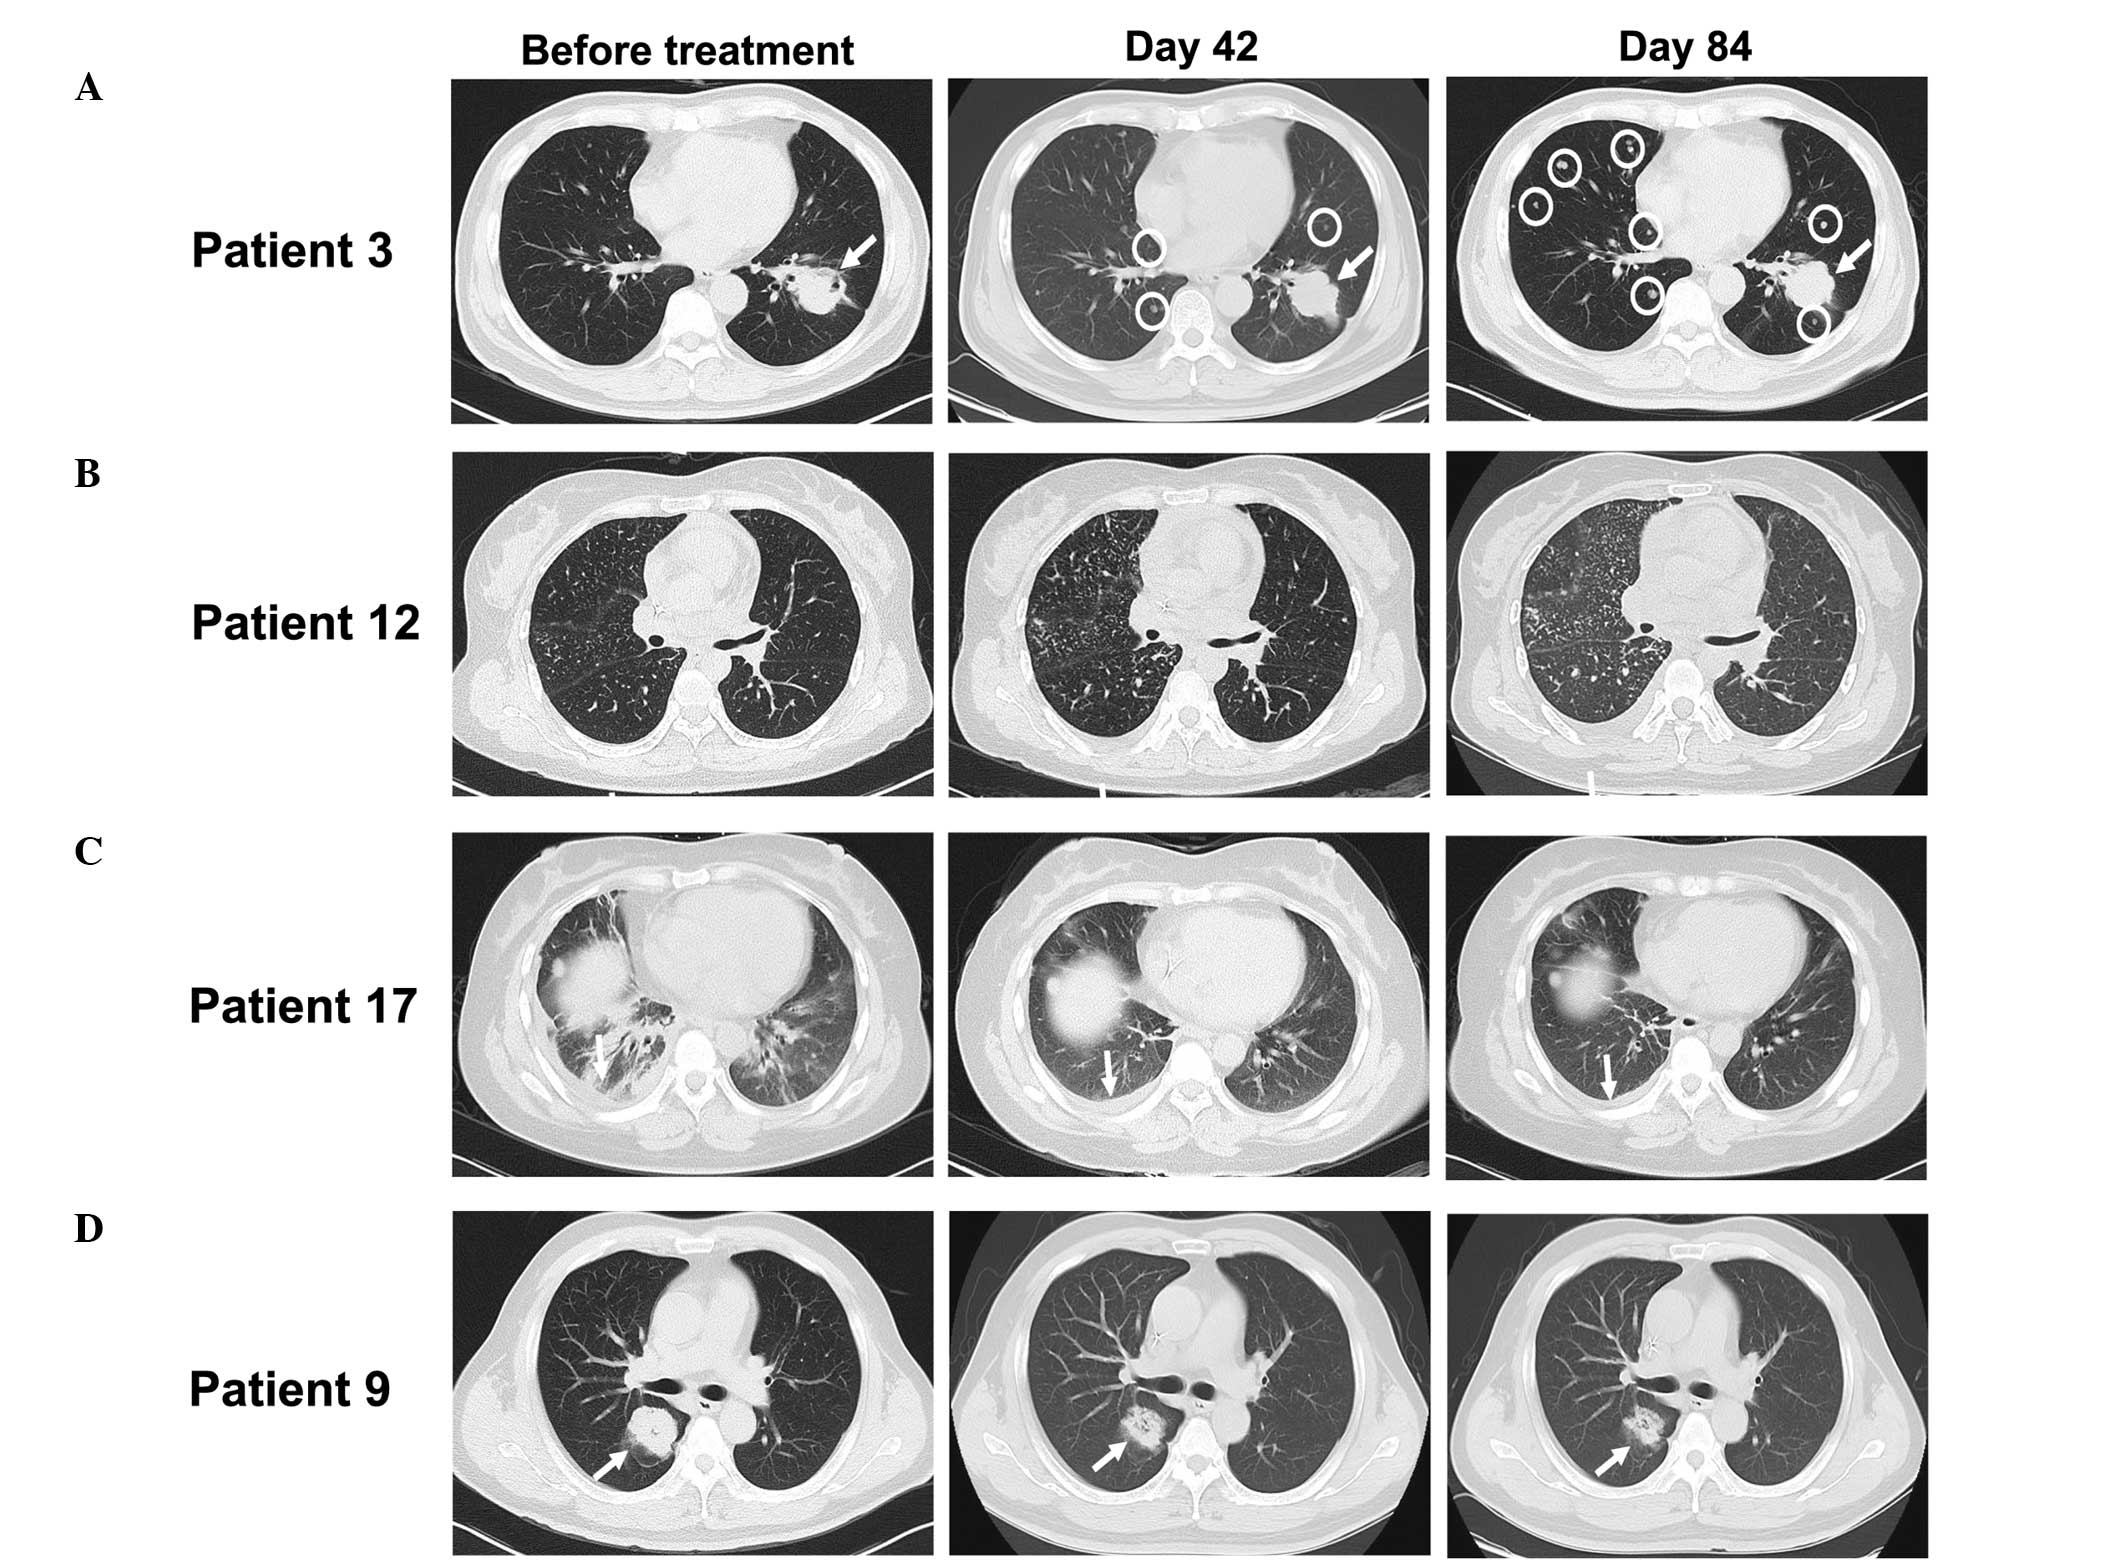

View Figures

Figure 1

Figure 2

Figure 3

Figure 4